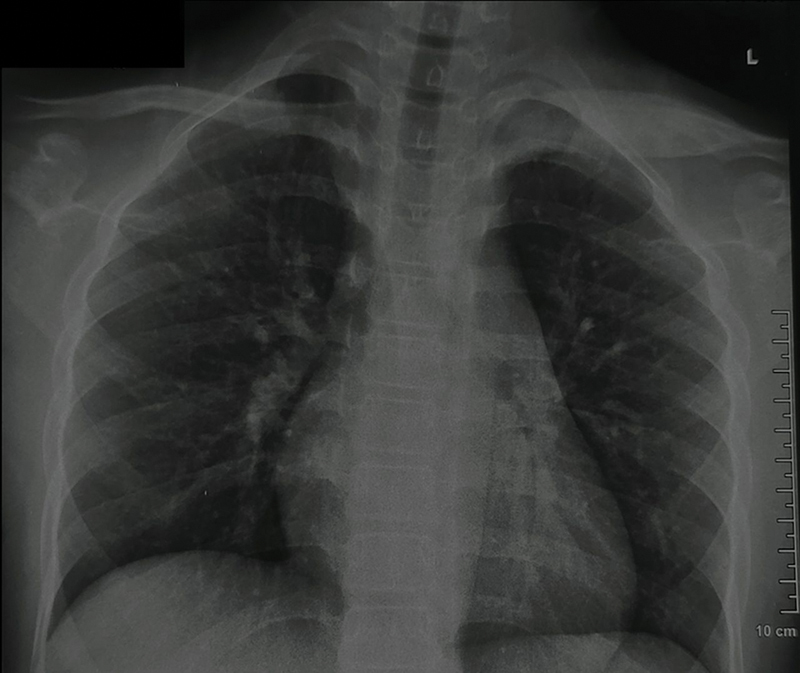

慢性非感染性骨髓炎或慢性非细菌性骨髓炎(CNO),也称为慢性复发性多灶性骨髓炎,是一种主要影响儿童年龄组的自身炎症性骨疾病。目前,该病的诊断主要基于临床、实验室和影像学特征。影像学在CNO的诊断和随访中起着至关重要的作用,全身磁共振成像(WBMRI)是主要方式。x光片有助于排除常见的鉴别诊断,如感染和恶性肿瘤。WBMRI有助于疾病检测和鉴别诊断的排除,识别额外的病变,并在确定骨骼受累模式方面发挥作用,有助于预测和分级。最近对WBMRI上特定形态和分布模式的认识越来越多地允许仅通过成像对该实体进行预先诊断。这也有助于在随访中评估对治疗的反应。本文旨在总结影像学在CNO评估中的作用,特别强调WBMRI在其评估中的作用。

Chronic noninfectious osteomyelitis or chronic nonbacterial osteomyelitis (CNO), also known as chronic recurrent multifocal osteomyelitis, is an autoinflammatory bone disorder primarily affecting the pediatric age group. Currently, it is diagnosed on the basis of clinical, laboratory, and imaging features. Imaging plays a crucial role in the diagnosis and follow-up of CNO with whole body magnetic resonance imaging (WBMRI) being the main modality. Radiographs assist in exclusion of common differential diagnoses like infections and malignancy. WBMRI aids in disease detection and exclusion of differential diagnoses, identifies additional lesions, and has a role in ascertaining the pattern of bony involvement which helps with prognostication and grading. Recent recognition of specific morphological and distribution patterns on WBMRI is increasingly allowing an upfront diagnosis of this entity to be made on imaging alone. It is also helpful for assessment of response to therapy during follow-up. This review aims to summarize the role of imaging in the evaluation of CNO, with special emphasis on WBMRI in its assessment.